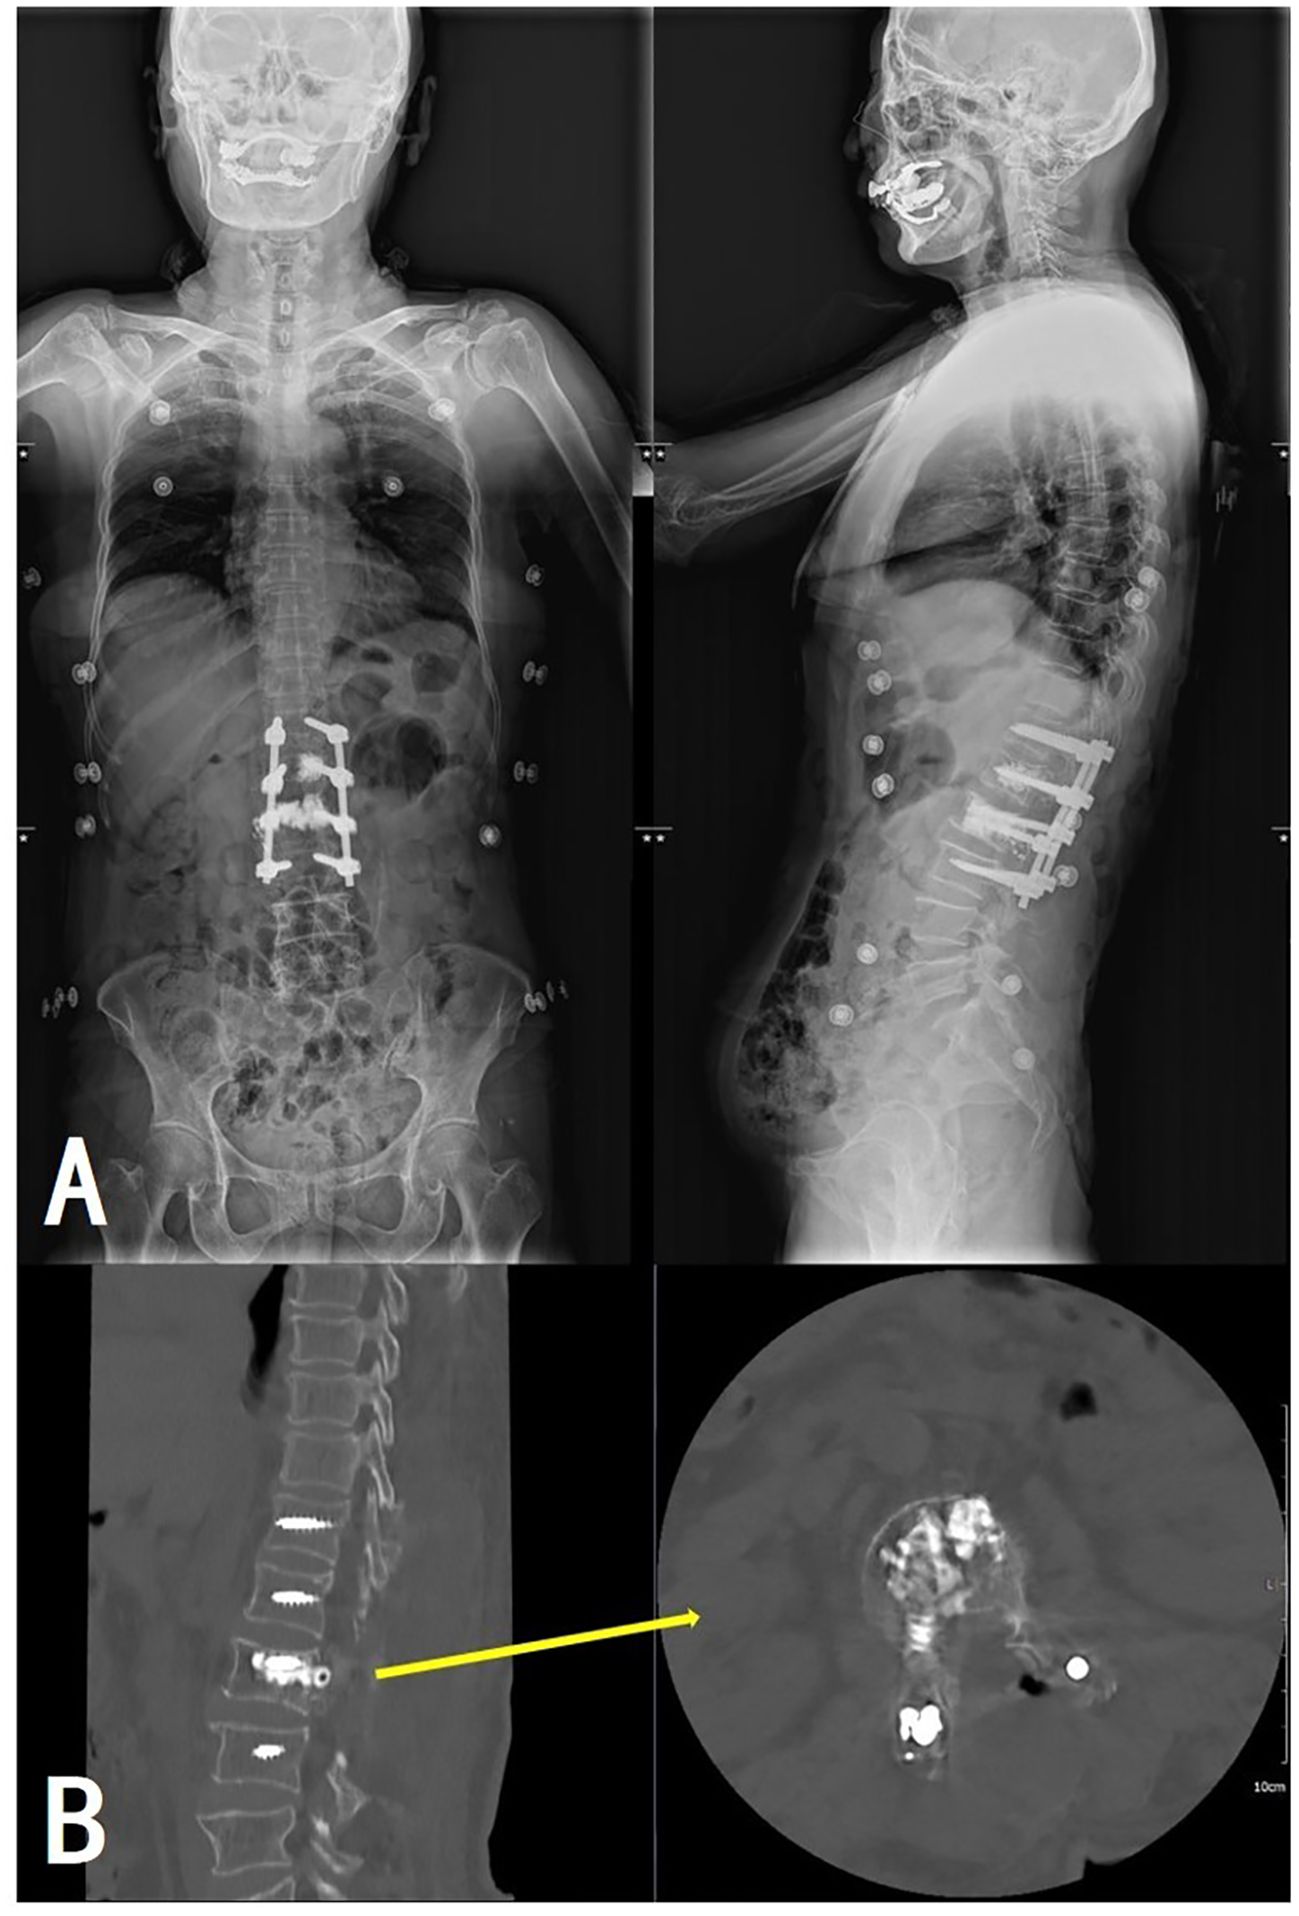

Pathological examination of tissue samples supported the diagnosis of AVH (Figure 5). The patient’s bilateral iliopsoas muscle strength recovered to grade V, and the pain and numbness symptoms were greatly alleviated, with a postoperative VAS of 2. Follow-up at 1.5, 6, and 12 months revealed good recovery of muscle strength and sensation, with no signs of recurrence (Figure 6).

Figure 6

Composite medical images showing spinal X-rays and CT scans. The upper row (A) includes front and side X-rays of the torso, highlighting spinal hardware. The lower row (B) presents detailed CT scans of the spine, with a yellow arrow indicating a specific vertebral area.

Figure 6. Postoperative full-length spinal X-ray (A) and lumbar CT (B) revealed satisfactory positions of the internal fixation and the bone cement without extravertebral leakage.